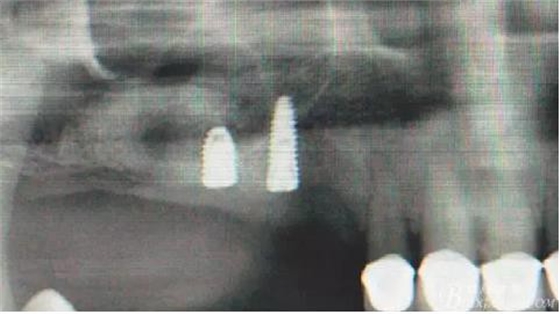

術(shù)后X光片。

術(shù)后40天X光片。